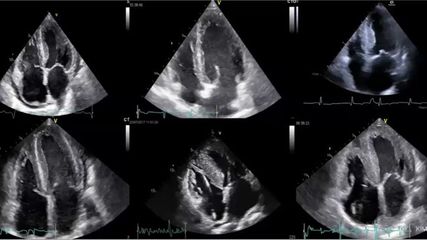

Fokus: hypertrophe Kardiomyopathie

In unserem Fokus zur hypertrophen Kardiomyopathie (HCM) haben wir für Sie relevante Artikel zu dieser Erkrankung zusammengestellt. Anlässlich neuer therapeutischer Möglichkeiten gewinnen ...

E-Learning: seltene hypertrophe Kardiomyopathien

Diese Zusammenstellung von DFP-Kursen zu Diagnostik und Therapie der kardialen Amyloidose hilft Ihnen, Patienten mit kardialer Amyloidose möglichst frühzeitig zu identifizieren.